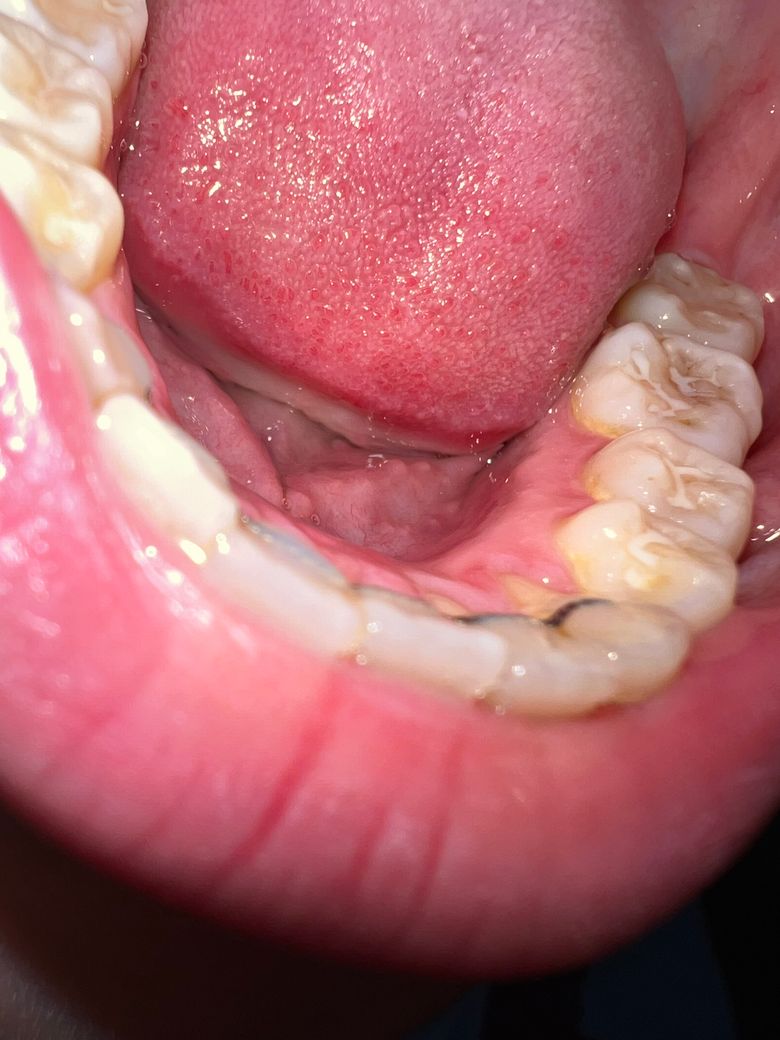

하악 어금니 갈색, 씹는면 충치인가요?

왼쪽 하악 씹는면의 치아가 어느순간부터 시리기 시작했는데요. 1년전 해당 증상이 생겼을때 충치가 없다고 했고, 가장 마지막으로 검진받은 6개월 전에도 별 문제 없다고 넘어갔는데 오늘 보니 충치같이 생긴 것 같아서요.

최근엔 시린 증상이 아예 없습니다.

현재 사진상으로는 충치보다는 변색일 가능성이 높아보이고 치료받은지 오래되어 그런 것 같습니다.

치아에 치석도 많이 껴잇고 잇몸에 염증이 있어서 그럴수도 잇으니 치과에 가셔서 스켈링 및 잇몸치료를 받아보시는게 좋을것같습니다.

사진으로 봤을 경우에는 큰 충치가 보이지는 않습니다. 하지만 내부에 충치가 있을 수도 있기 때문에 치과에서 정확한 검사를 받아보는 것이 좋습니다

충치의 양상은 아닌 것 같고 변색, 착색에 가까울 것 같습니다. 치과가서 스케일링 해보고 엑스레이 찍어보고 판단하면 될 것 같습니다.